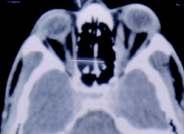

Fig 2 — CECT Scan (Axial Section) Showing Exophthalmos and Enlarged Medial Rectus and Inferior Rectus Muscles